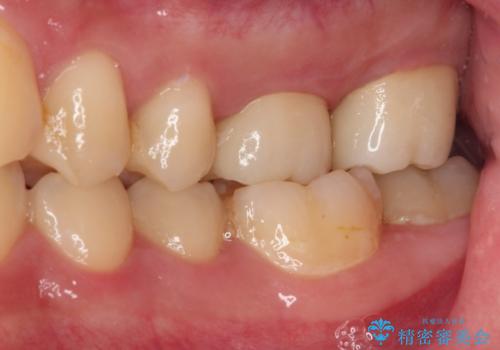

2,3回の処置後には来院時に感じていた痛みはなくなり、根管治療から半年後にはレントゲンでの根尖部病変も消失していました。

はじめに処置をしていた医院に通っていたら、2本とも抜歯されていたかと思うとゾッとするおっしゃっていました。